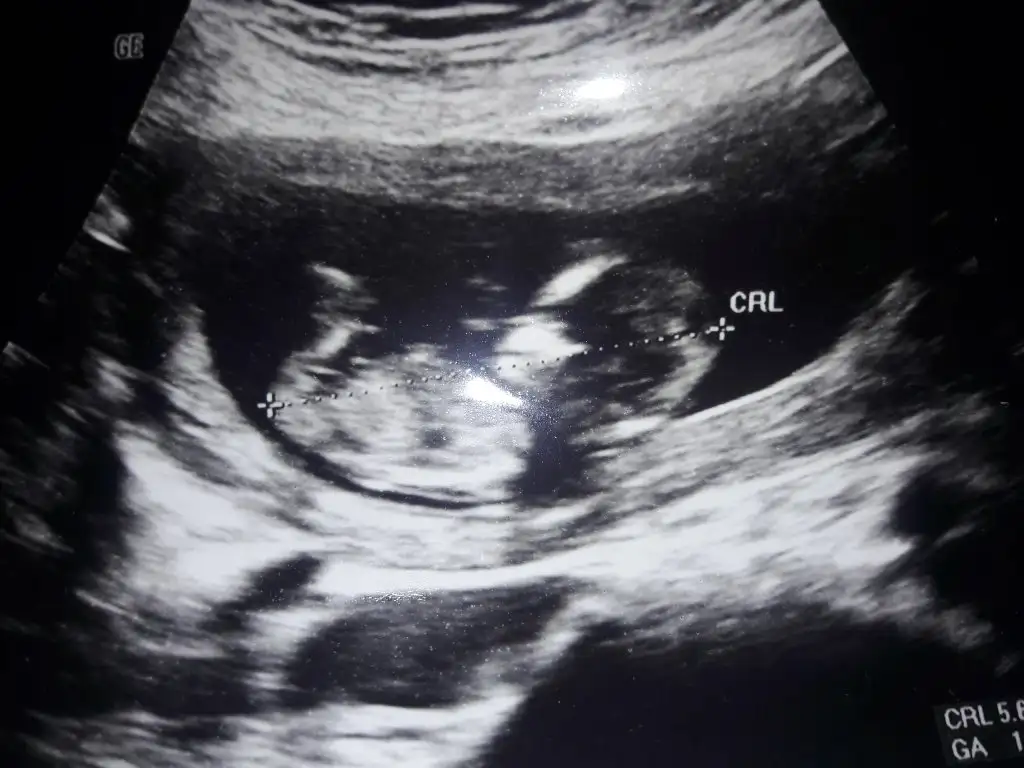

Erkek görünüyorIkra meyra

Teşekkür ederimErkek görünüyor

Teşekkür ederim siz nub teorisine göre mi tahmin yapıyosunuzKız sanki

Teşekkür ederimKız sanki